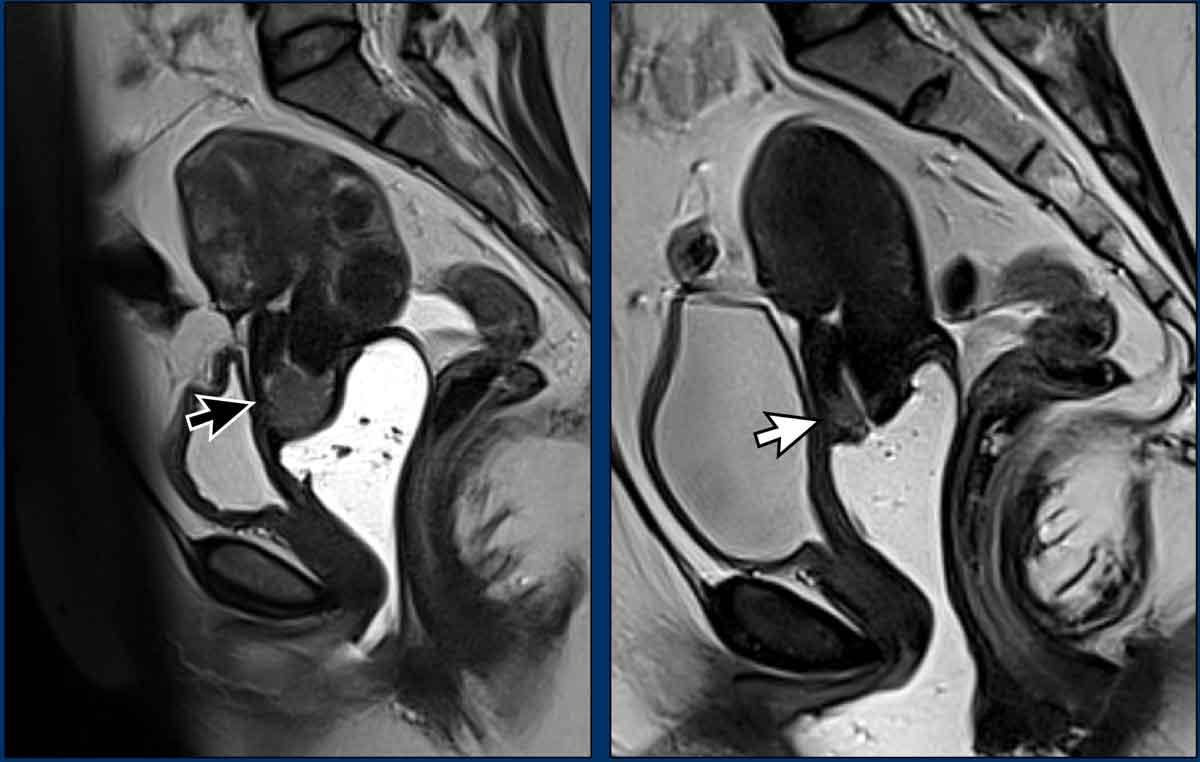

Hình ảnh

MRI trước điều trị (bên trái) cho thấy khối u cổ tử cung dạng sùi (exophytic) với tín hiệu trung gian.

MRI sau điều trị (bên phải) cho thấy khối u đã được thay thế hoàn toàn bởi mô xơ giảm tín hiệu.

Không còn tín hiệu trung gian của mô u.

Chuỗi xung DWI có thể hỗ trợ xác nhận sự vắng mặt của khối u.

Trong trường hợp đáp ứng hoàn toàn, bệnh nhân không cần phẫu thuật thêm.

Lưu ý rằng trong trường hợp này, chụp MRI được thực hiện sau khi bơm gel nội âm đạo.

Kỹ thuật này không được khuyến cáo thường quy, nhưng có thể được cân nhắc áp dụng để hỗ trợ đánh giá khả năng xâm lấn phần trên âm đạo.

Trong một số ít trường hợp, phác đồ điều trị chuẩn gồm hóa xạ trị đồng thời kết hợp xạ trị áp sát không đủ hiệu quả và nghi ngờ còn tổn thương tồn lưu, như minh họa trong ví dụ dưới đây.

MRI trước điều trị (bên trái) cho thấy khối u cổ tử cung dạng sùi với tín hiệu trung gian (mũi tên đen).

MRI sau điều trị (bên phải) cho thấy một khối tín hiệu trung gian trên T2 tồn lưu nhỏ nhưng quan sát rõ ràng, cho thấy khối u chưa được thay thế hoàn toàn bởi mô xơ (mũi tên trắng).

Bệnh nhân được chỉ định phẫu thuật, đây là phương pháp điều trị chuẩn cho các bệnh nhân có đáp ứng không hoàn toàn sau hóa xạ trị đồng thời kết hợp xạ trị áp sát.

Chuỗi xung DWI có thể hỗ trợ phát hiện u tồn lưu sau hóa xạ trị đồng thời.

Lưu ý rằng thời điểm được khuyến cáo để đánh giá đáp ứng sau hóa xạ trị đồng thời là từ 4 đến 6 tuần sau khi kết thúc điều trị.